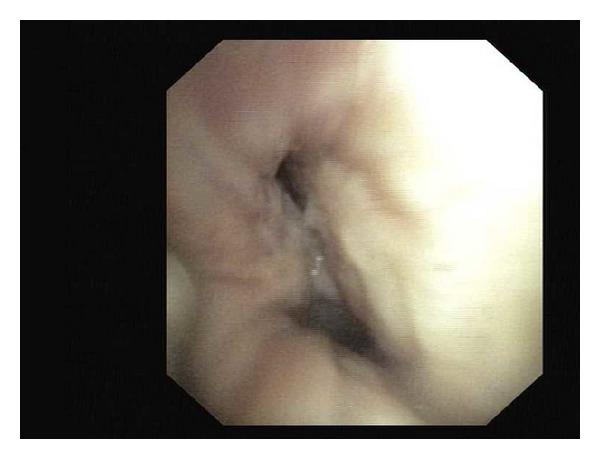

A 63-year-old female smoker was evaluated for lump over the right breast, fine needle aspiration cytology of which showed infiltrating ductal carcinoma. Investigations also revealed the presence of left upper lobe mass lesion, the biopsy of which suggested small cell carcinoma. The existence of two malignancies having different histopathologies at anatomically distinct sites suggests the diagnosis of dual primary malignancy involving the breast and the lung which, being a rare combination, prompted us to report the case.

一名63岁的吸烟女性因右乳肿块接受评估,其细针穿刺细胞学检查显示为浸润性导管癌。检查还发现左上叶有肿块病变,活检提示为小细胞癌。在解剖学上不同部位存在两种具有不同组织病理学的恶性肿瘤,提示诊断为涉及乳腺和肺部的双原发性恶性肿瘤,这种罕见的组合促使我们报告该病例。